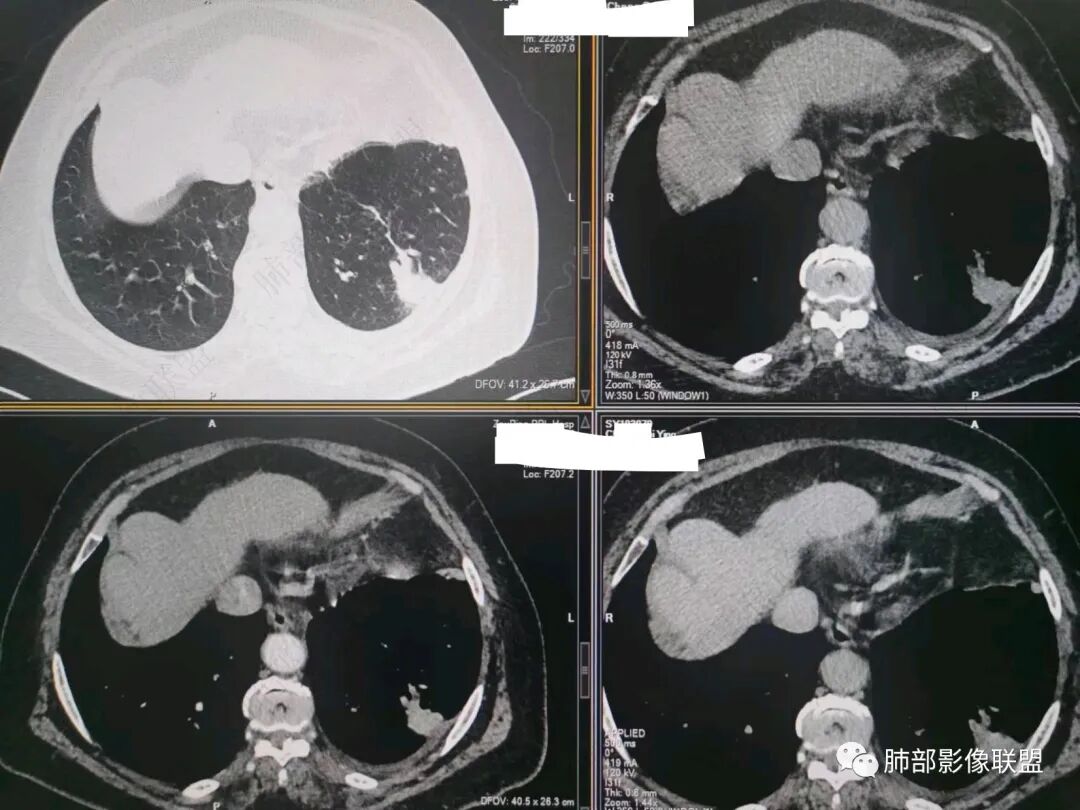

这就栽赃。都突到外面去了。

看看这个,骨头都侵袭了。

南边:一般这类侵袭,是中央地带毛刷状延伸到胸膜内。

我只是邓较瘦:南大这个我感觉局部似乎是栽赃呢 箭头那里是啥?

南边:栽赃是这样过去的,中间不会脂肪间隙清晰。

胸壁的组织,除非你怀疑胸壁转移结节。

转移淋巴结。

局部侵犯。有差异。

我只是邓较瘦:这个是侵犯出去不是淋巴结吧?

南边:不是,你看看强化与淋巴结不一致。

我只是邓较瘦:强化与肿瘤差不多。

南边:是。